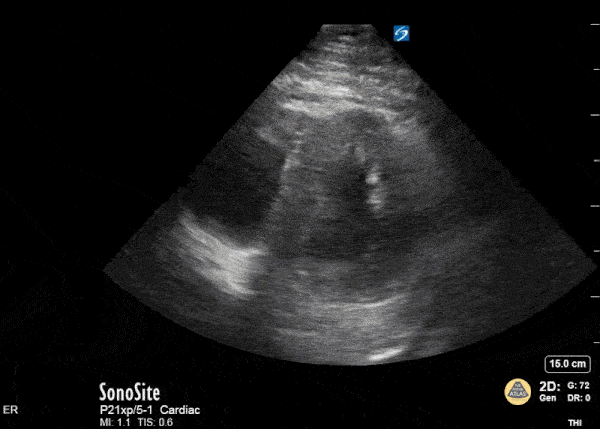

76F Prev Breast CA refer for cellulitis but ED +PCE, cardio for urgent ?tap

Which one are you not concerned about?

What's the pulsus?

IVC and Pericardial Effusion

Evidence: http://pocusjournal.com/article/2016-01-03p12/

Example: http://www.thepocusatlas.com/pericardium

Tutorial: https://web.stanford.edu/group/ccm_echocardio/cgi-bin/mediawiki/index.php/Tamponade

IVC plethora – Dilatation and less than a 50 percent reduction in the diameter of the dilated inferior vena cava (IVC) during inspiration, reflecting a marked elevation in central venous pressure, is frequently seen in patients with cardiac tamponade In one report, IVC plethora was associated with pulsus paradoxus and was present in 92 percent of those with pericardial effusion who required pericardial drainage.

It is highly sensitive but not at all specific for cardiac tamponade